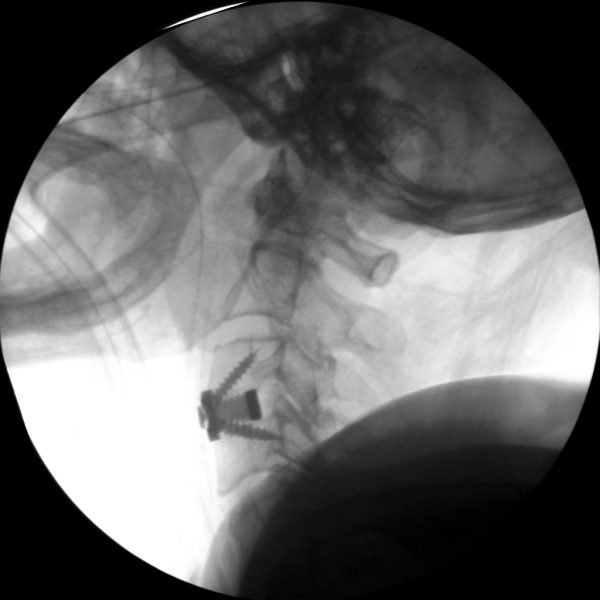

High-quality imaging

Skan-C uses advanced imaging technology, such as pulsed fluoroscopy and digital subtraction angiography, to provide highly detailed images of the affected area. This allows doctors to perform procedures with increased precision and accuracy, and better patient outcome

Clinical Evidence

Skan-C is a great C-arm for neurology treatments for several reasons